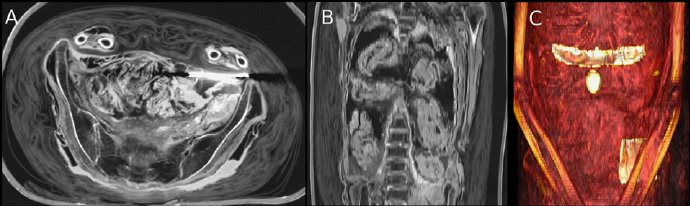

Preserved remnants of a 13th century autopsy…

And a CT scan of the same:

Wade and Nelson, Radiological evaluation of the evisceration tradition in ancient Egyptian mummies, 2013. These CT scans were performed on the mummy Djedmaatesankh, an ordinary woman from Thebes who died almost 3000 years ago. The body was eviscerated and filled with packages which possibly contained organs. A scarab and falcon were placed on the abdomen external to the body cavity.